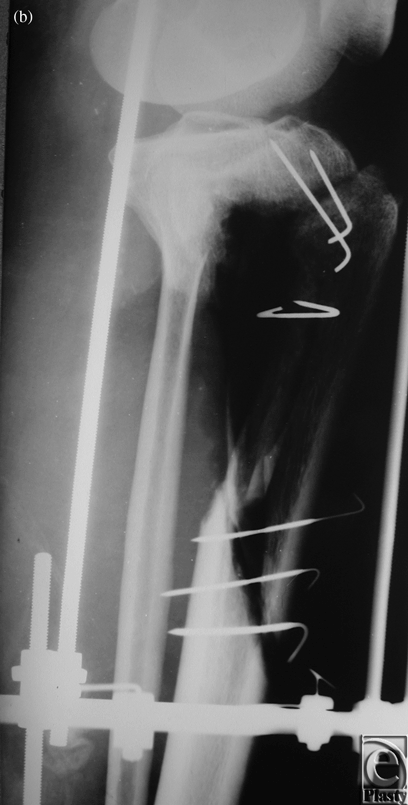

Case 2: Trauma of the lower leg

The patient was a 35-year-old woman who suffered from necrosis of both the tibia and fibula as a result of open trauma. Full debridement and temporary full-thickness skin grafting were performed in primary hospitals before we applied our 2-stage method. After correcting the deformities by applying the Ilizarov device in our hospital, an 18-cm fibula osteoseptocutaneous flap was found to be necessary and was transferred from the contralateral side. End-to-end anastomoses were performed between peroneal and posterior tibial vessels (Figs 2a-2f).